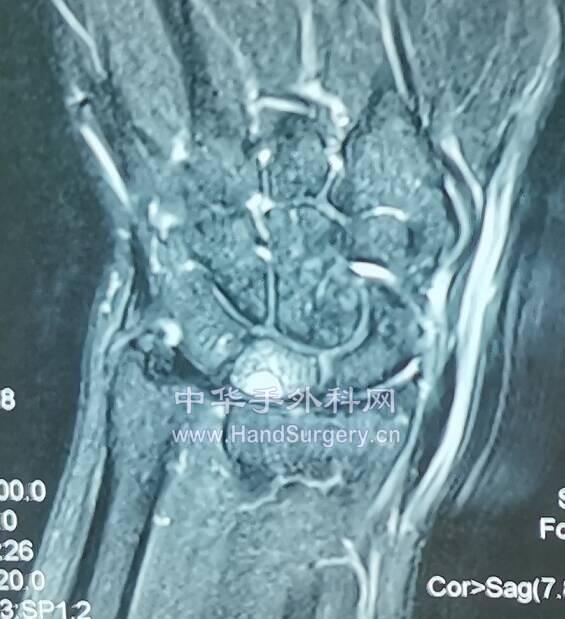

月骨坏死III期

微信截图_20200620170439.png

微信截图_20200620170520.png

微信截图_20200620170555.png